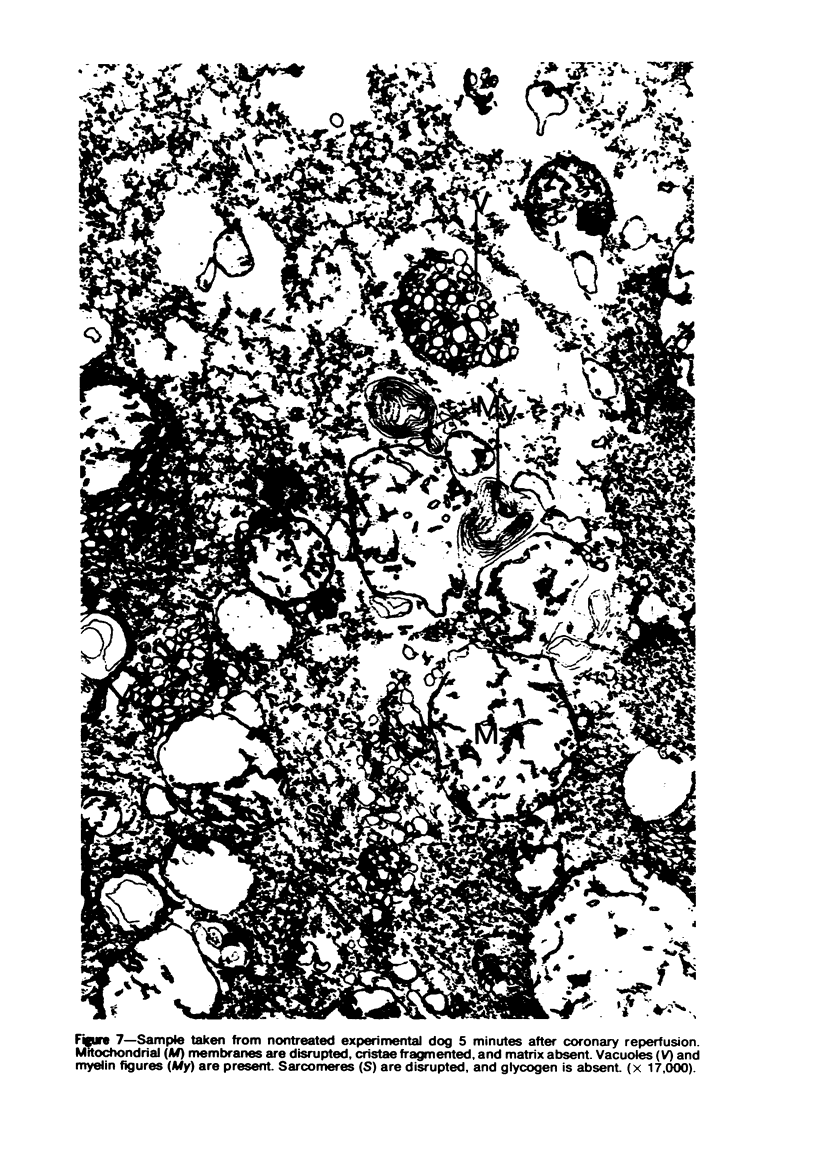

The effects of lidocaine infusion on the ultrastructural damage induced in cardiac muscle by normothermic cardiopulmonary bypass were assessed in 15 dogs. Six dogs received no medication other than sodium pentobarbital (25 mg/kg, intravenously) while 9 dogs were treated with lidocaine after anesthesia. Lidocaine was given as a 2-mg/kg loading dose 10 minutes prior to ischemic arrest and a 2-mg/min continuous infusion during the entire experimental period. Biopsy samples of the left ventricular apex were taken 15 and 45 minutes after the start of ischemic arrest and 5 minutes after resumption of coronary blood flow. Biopsy samples were also obtained from 4 animals after thoracotomy to serve as controls for experimental procedures. Myocardial ultrastructure in the 4 control animals was comparable to that reported by other investigators. Five of 6 of the nontreated dogs and 8 of 9 lidocaine-treated dogs survived the entire period of ischemia and 5 minutes of coronary reperfusion. However, the extent of ultrastructural damage varied considerably between the two groups. In the experimental dogs receiving no lidocaine, mitochondria were swollen, cristae were absent, the mitochondrial matrix was cleared, and sarcomeres were disrupted. Myelin figures and contraction bands were also observed. None of the surviving lidocaine-treated animals had ultrastructural changes comparable to the worst ones in nontreated dogs. Damage was limited to some swelling of mitochondria with focal clearing of matrix. Most cristae remained intact. There were no myelin figures and few contraction bands. The results suggest that lidocaine protects the integrity of ischemic myocardium. It is suggested that this protection resulted from stabilization of plasma and/or mitochondrial membranes. (Am J Pathol 87:399-414, 1977).